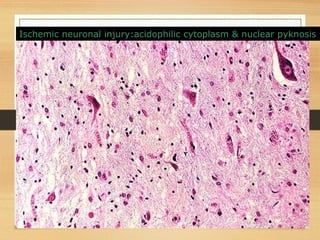

Ischemic neuronal injury:acidophilic cytoplasm & nuclear pyknosis

… a mess - so many

cells have died - the

tissue is not

recognizable. Nuclei

have become pyknotic

(shrunken and dark),

undergone karorrhexis

(fragmentation) and

karyolysis(dissolution)